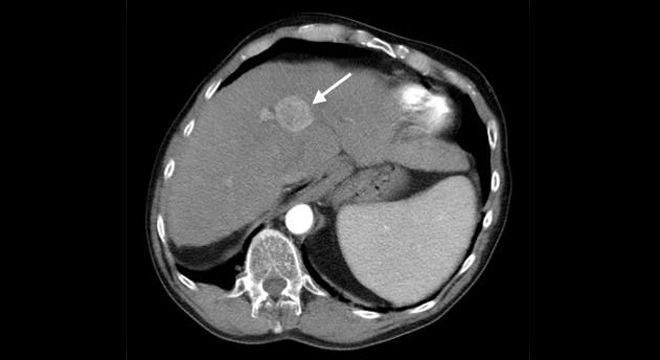

Leberkrebs: Computertomographie zeigt Tumor in der Leber

• Computertomographie (CT)